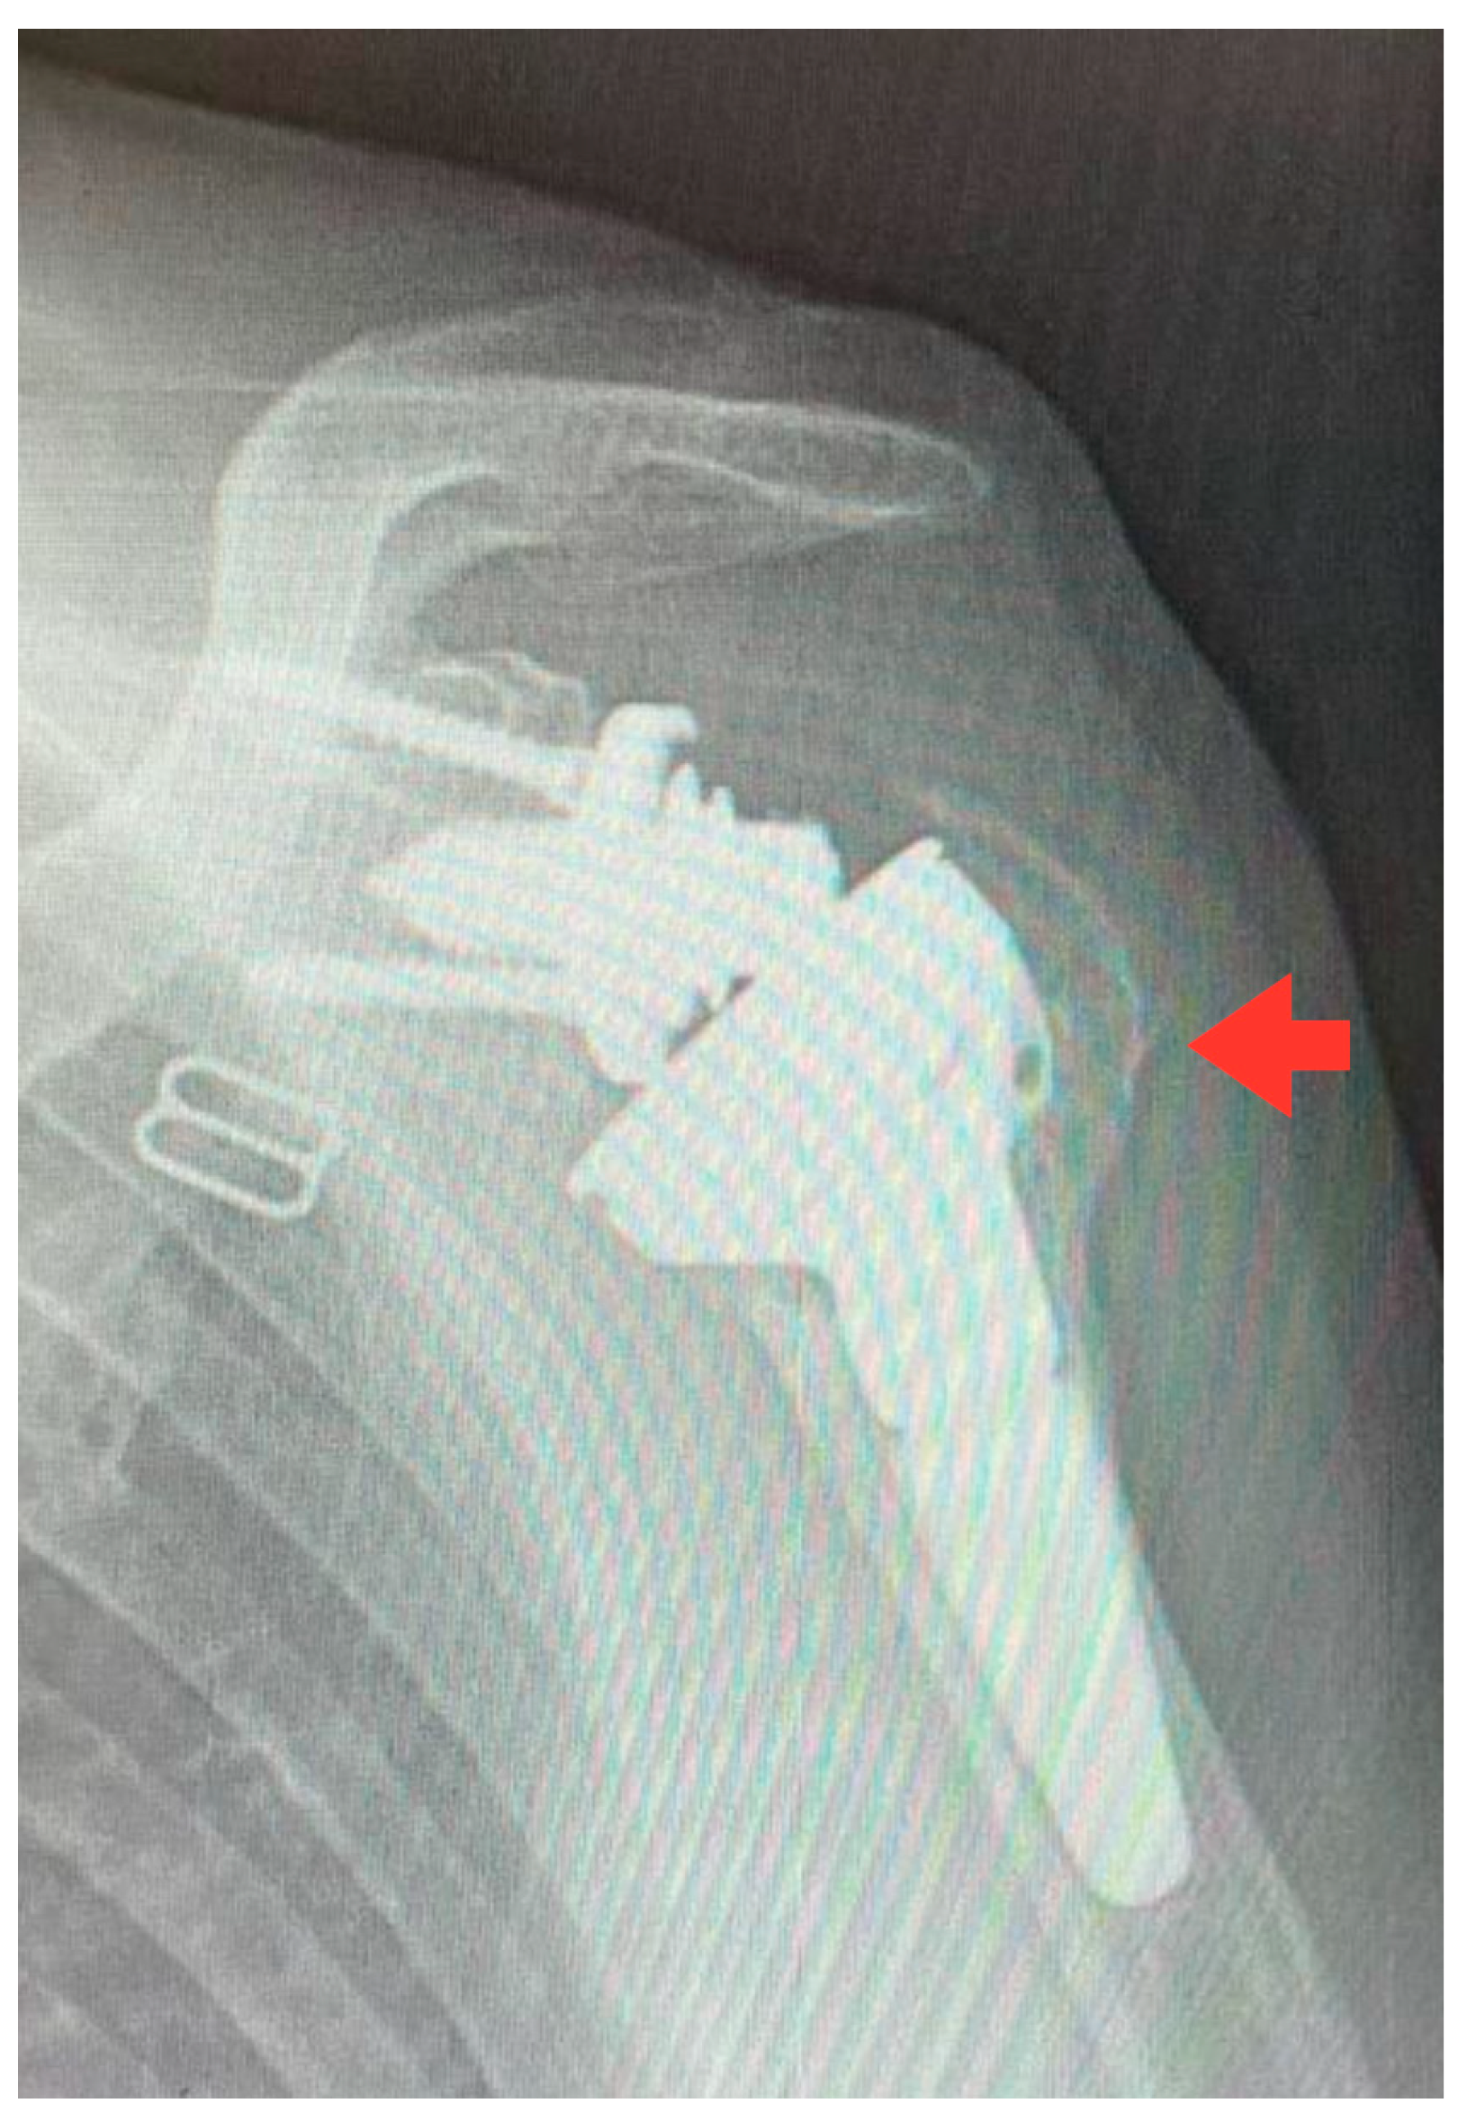

3.2. Radiological Outcomes

4.2. Radiological Outcomes